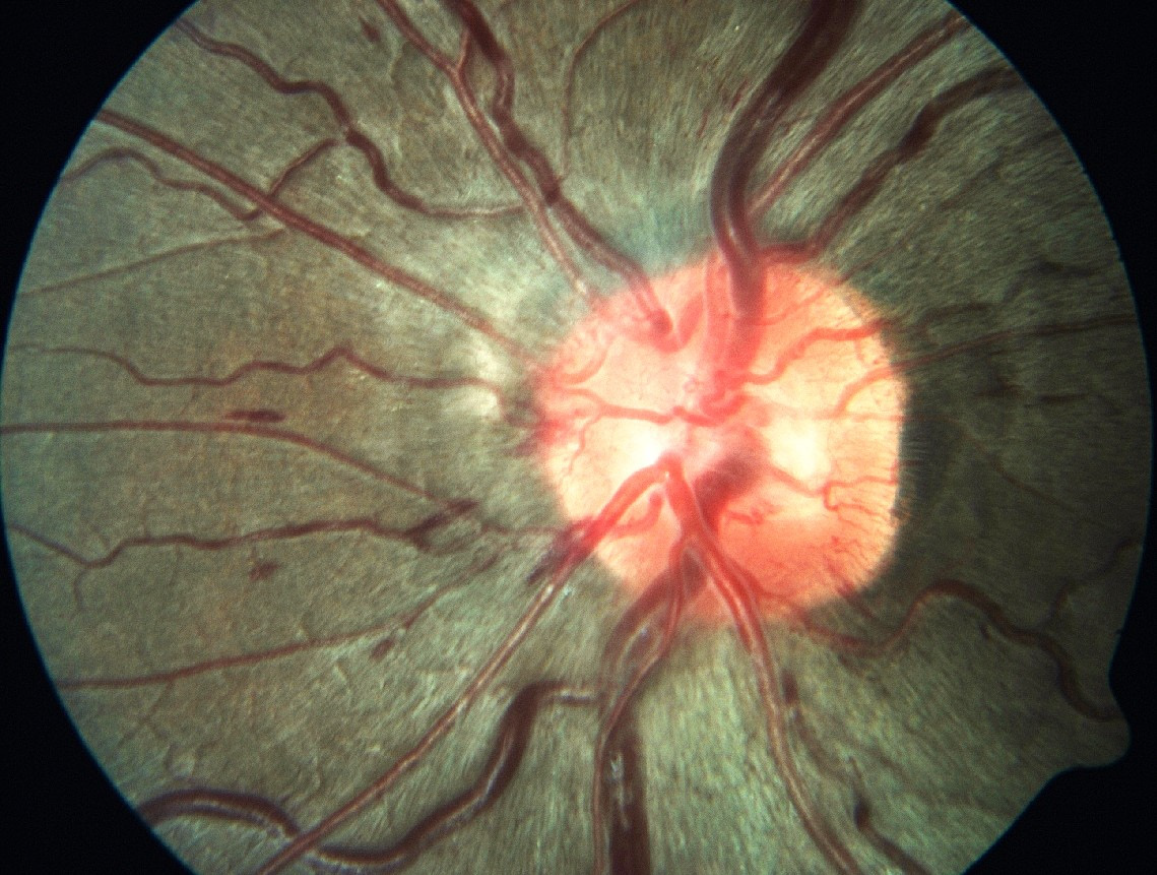

Figure 2 Fundus photograph demonstrating optic disc edema.

A hallmark feature of spaceflight-associated neuro-ocular syndrome, attributed to cephalad fluid redistribution, venous congestion, and altered peri-optic cerebrospinal fluid dynamics in microgravity.